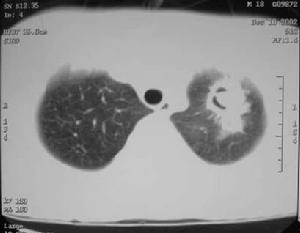

(3)氣管插管、氣管切開、人工呼吸器的套用。靜脈導管的留置、動脈內導管,導尿管留置;燒傷創面。各種插管檢查,如內鏡檢查、插管造影或內引流管的安置等都可破壞局部屏障防禦功能,有利於病原菌的入侵。

(4)嚴重的原發疾病,如肝硬化、結締組織病、糖尿病、尿毒症、慢性肺部疾病等也是敗血症的誘因。如患者同時存在二種或二種以上誘因時,發生敗血症的危險性將明顯增加。在上述各種誘因中靜脈導管留置引起的葡萄球菌敗血症,在院內感染敗血症中占重要地位,靜脈導管留置72小時以上者局部可發生靜脈炎,由此可誘發敗血症;靜脈導管留置和輔助呼吸器的套用亦是不動桿菌屬、沙雷菌屬等革蘭陰性敗血症的常見誘因之一;留置導尿管則常是大腸埃希菌、銅綠假單胞菌敗血症的誘因。長期腎上腺皮質激素和廣譜抗菌藥物的套用是誘發真菌敗血症的重要因素。

(二)細菌因素。金葡菌可產生多種每和外毒素,其中起主要致病作用的有血漿凝固酶、α—溶血毒素、殺白細胞素、腸毒素(A—E,以A型多見)、玻脫性毒素、紅疹毒素等可導致嚴重的敗血症;近年來分離到的腸毒素F,與中毒性休克綜合徵(TSS)的發生有關。格蘭陰性桿菌所產生的內毒素能損傷心肌和血管內皮,激活補體系統、激肽系統、凝學與纖溶系統,以及交感腎上腺脊質系統,ACTH/內啡肽系統等,並可激活各種血細胞和內皮細胞。產生多種細胞因子(如TNF—α,IL—1,IL—6、IL—8等各種細胞因子,其中TNF—α在病理勝利改變中起關鍵性作用),炎症介質、心血管調節肽等,導致微循環障礙、感染性休克等。銅綠假單胞蛋白質合成抑制物,如蛋白酶、殺白細胞素、磷脂酶C及外毒素A等,後者是一很強的蛋白質合成抑制物,可引起組織壞死;外毒素A和彈性蛋白酶同時存在時,其毒力最大,肺炎球菌致病主要依賴其,後者有抗吞噬作用;常可產生溶血毒素和神經氨酸酶。肺炎克雷伯桿菌等亦具有,有節抗吞噬和體液中殺菌物質的作用。病理變化病原菌的毒素可引起組織和臟器細胞變形,可發生水腫、壞死和脂肪變形。毛系血管損傷造成皮膚和年末淤點和皮疹。病菌引起的遷徙性多見於肺、肝、腎、骨、皮下組織等處,可並發心內膜炎、腦膜炎、骨髓炎等。單核—吞噬細胞增生活躍,肝脾均可增大。